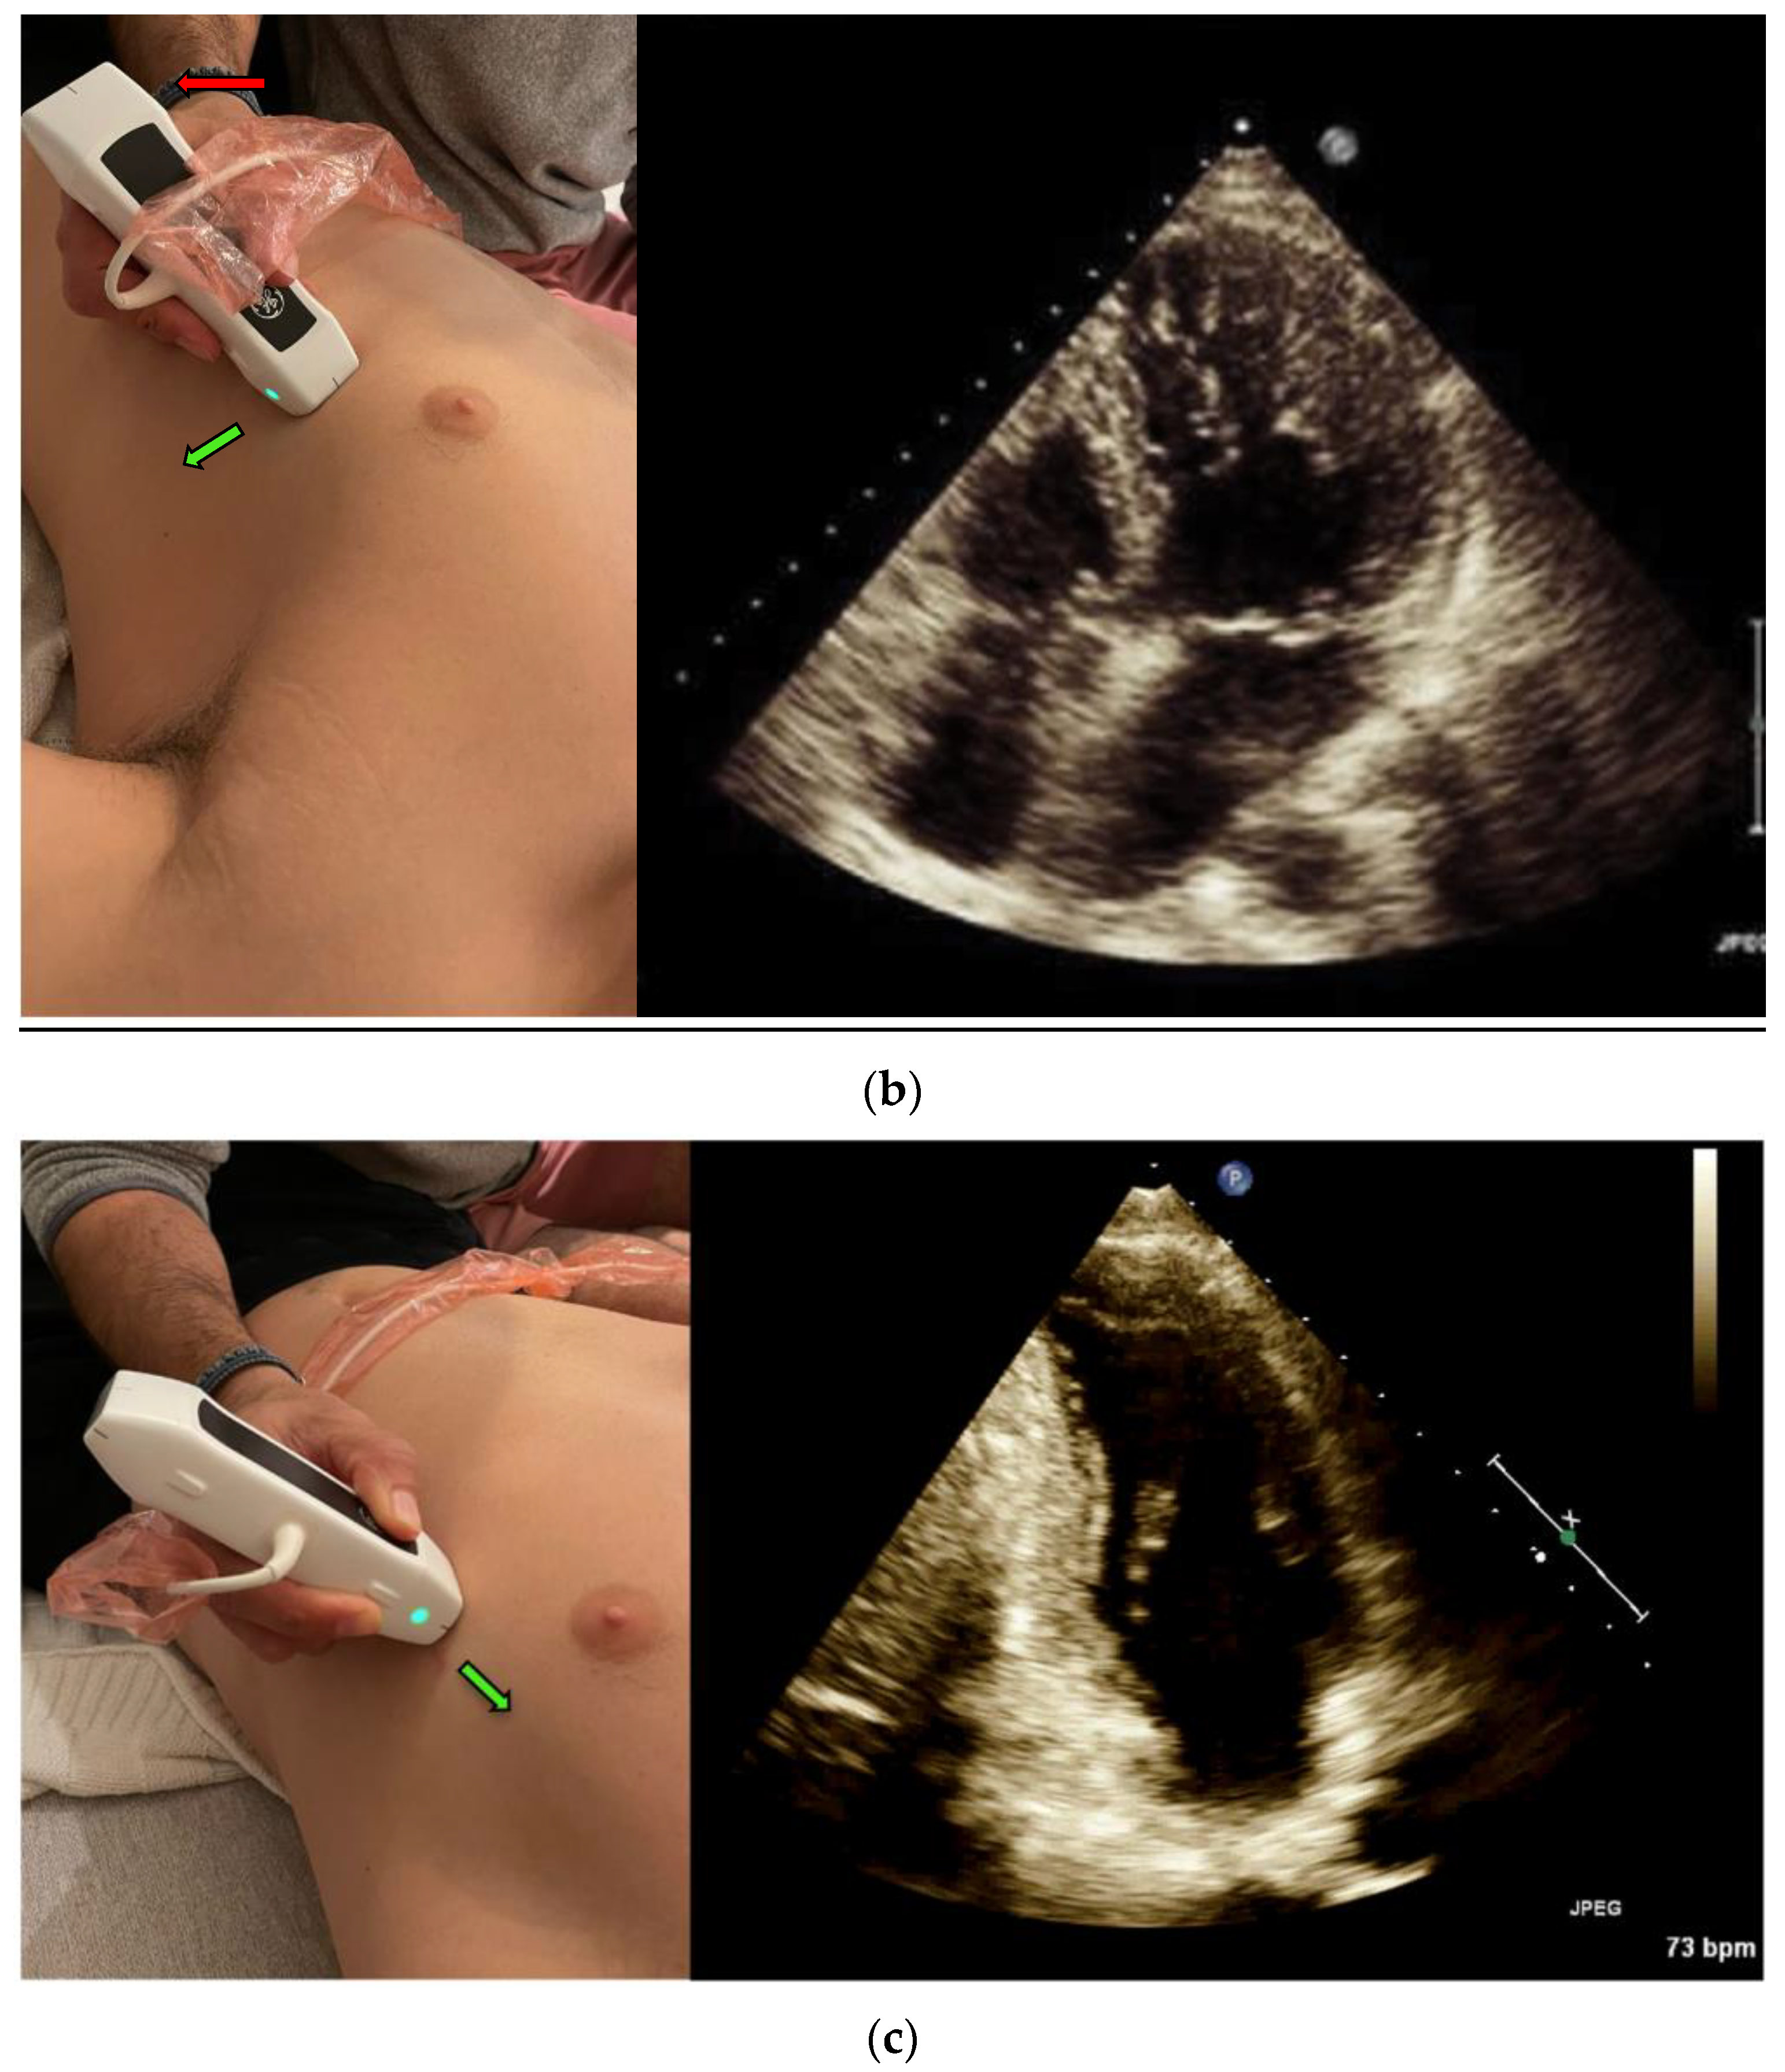

Left ventricular (LV) Ejection Fraction is an important clinical index. EF assessment can be extremely valuable in evaluating hemodynamically unstable patients [12] and dyspneic patients [4]. It can also diagnose heart failure in different settings, such as the emergency department and the internal wards [13,14]. The classic method for measuring EF is the Simpson method, which requires manually tracing the endocardial border of the left Ventricle in systole and diastole in both the apical four-chamber view (Figure 1a) and the apical two-chamber view (Figure 1c) [15].

The Velocity Time Integral (VTI) is classically measured at the apical five-chamber view (Figure 1b) by measuring the flow velocity through the left ventricle outlet (LVOT), which provides a velocity over time curve. Multiplying the VTI times the left ventricular outlet area equals the cardiac stroke volume, and if multiplied by the heart rate—the cardiac output [22]. The cardiac stroke volume aids in the differentiation of shock, shock treatment, determining fluid responsiveness, and in risk stratification [23,24]

3. Real-Time EF Measurement

A POCUS expert acquired apical four-chamber view (A4CV) clips by placing the probe horizontally over the apex of the heart (Figure 1a) and prospectively recording for at least 10 s. All clips were reviewed and blindly assessed for LVEF quantification by the Expert without exposure to the automatic tool results. Post hoc automatic analyses were performed and documented using the Venue™ real-time automatic LVEF. Each clip was considered an independent observation point.

5. VTI Measurement

An expert POCUS operator acquired the views by placing the probe horizontally in the apex of the heart and prospectively recording for at least 10 s in the apical five chambers view (Figure 1b). Half of the clips were scored by the physician to quality distribution from zero to two: 0—low for a failed attempt to obtain a proper reading of the VTI or image that could not be analyzed, 1—medium for VTI can be calculated but with moderate imaging quality and 2—high for good quality clips with a clearly demonstrated VTI. The clips were then blindly measured, tracing the LVOT velocity curve manually for VTI. The automatic tool measured the same clip, which similarly scored the clips according to imaging quality. High- or medium-quality clips were then further assessed and automatically calculated for LVOT VTI values. Each clip was considered an independent observation point.

Figure 1. (a) Acquisition and anatomy of the Apical Four Chamber View. (b) Acquisition and anatomy of the Apical Five Chamber View (similar acquisition to Apical Four Chamber View, with a slight upward tilt of the probe). (c) Acquisition (probe point—green arrow) and anatomy of the Apical Two Chamber View.